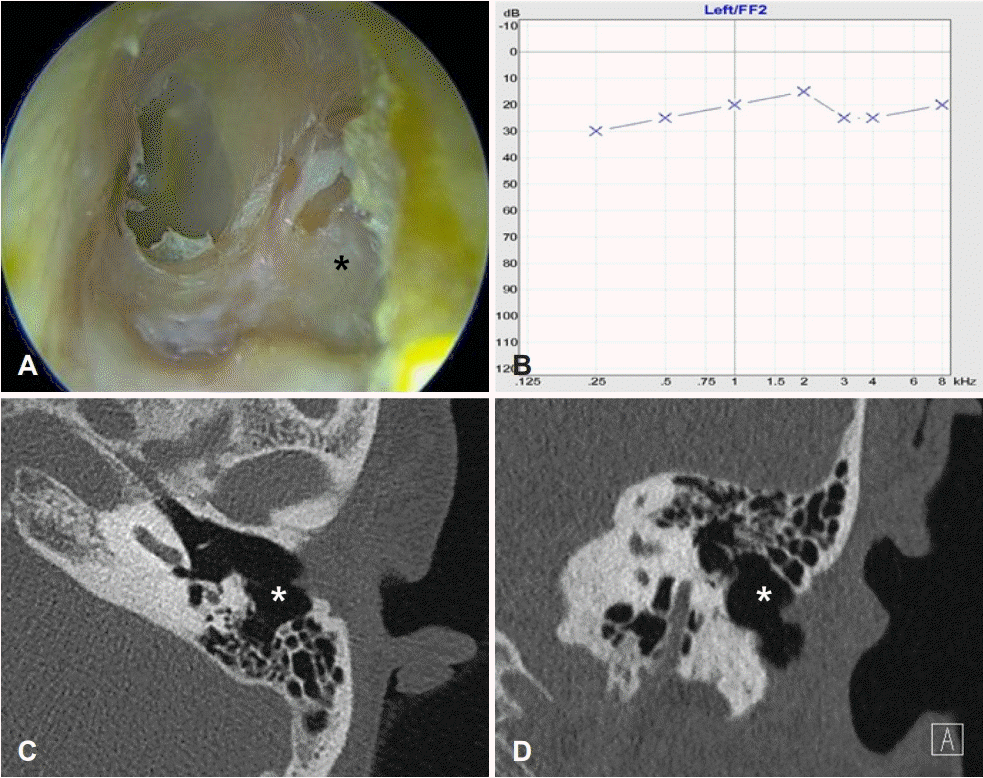

초진 40개월 후에 좌측 이루와 가려움이 발생했고 진찰상 골성 외이도 후벽의 결손부위는 변화가 없었으나 노출된 유양돌기 점막의 부종과 이루가 분비되는 소견이었다(Fig. 2A). 순음청력검사상 정상 청력으로 유지되었으나(Fig. 2B) 측두 골컴퓨터단층촬영상 기존의 좌측 골부 외이도 후벽 결손과 함께 유양돌기 및 중이에 연부조직 음영이 관찰되어(Fig. 2C and D), 외이도 후벽 결손을 통한 이차적 중이염 및 유양돌기염으로 진단하고 염증의 제거 및 골부 외이도 재건을 위해 수술을 계획하였다. 전신마취 후 후이개 접근법을 시행하였다. 절개 후 이개를 전방으로 견인 고정하고 측두골 근막을 채취한 다음, 유양돌기 부위의 골막을 절개후 거상했다. 외이도 내부에 절개없이 다양한 거상기를 사용하여 외이도 피부를 골벽으로부터 분리한 후 약 2 mm 폭의 내측 외이도 피판으로 거상하고 단순 유양돌기절제술을 시행했다. 유양돌기쪽에서 골성 외이도 후벽의 결손이 상하방향으로 9 mm 및 내외방향으로 11 mm의 크기로 관찰되었고 유양돌기 내 육아조직을 모두 제거했다(Fig. 3A). 골성 외이도 결손부의 내측 경계에 외이도를 재건할 이개 연골이 놓일 수 있도록 1 mm 지름의 절단 burr로 드릴하여 홈(groove)을 만들었다(Fig. 3B). 후이개 절개부위를 이개쪽에서 외측으로 박리하여 이개강(cavum concha)연골을 연골막이 부착된 채로 15×10 mm의 크기로 채취한 다음, 연골막의 외측 경계부를 연골에서 분리하고 골성 외이도 후벽 결손의 크기보다 상하 두 방향은 1 mm 정도 크게, 외측 방향은 3 mm 정도 크게 재단했다(Fig. 3C). 외이도 방향에서 준비된 이식물의 내측 경계를 드릴로 만들어둔 홈(groove)에 맞추고 측두근막으로 덮어서 이식물을 고정시켰다(Fig. 3D and E). 고실외이도 피판을 원위치시키고 외이도를 나일론 거즈로 충전한 후, 탄력 붕대로 압박 드레싱하고 수술을 종료했다. 환자는 술후 5일째 별다른 문제 없이 퇴원했고 외래에서 수술 후 15일에 외이도 충전물을 제거했다.

Pre-operative findings of the patient. A and B: Transcanal endoscopic view in 40 months later shows discharge from the defect at posterior wall of left bony external auditory canal (bEAC) (A) with preserved hearing (B). C and D: Follow-up CT of the left temporal bone reveals sustained the defect with hazziness of mastoid cavity.